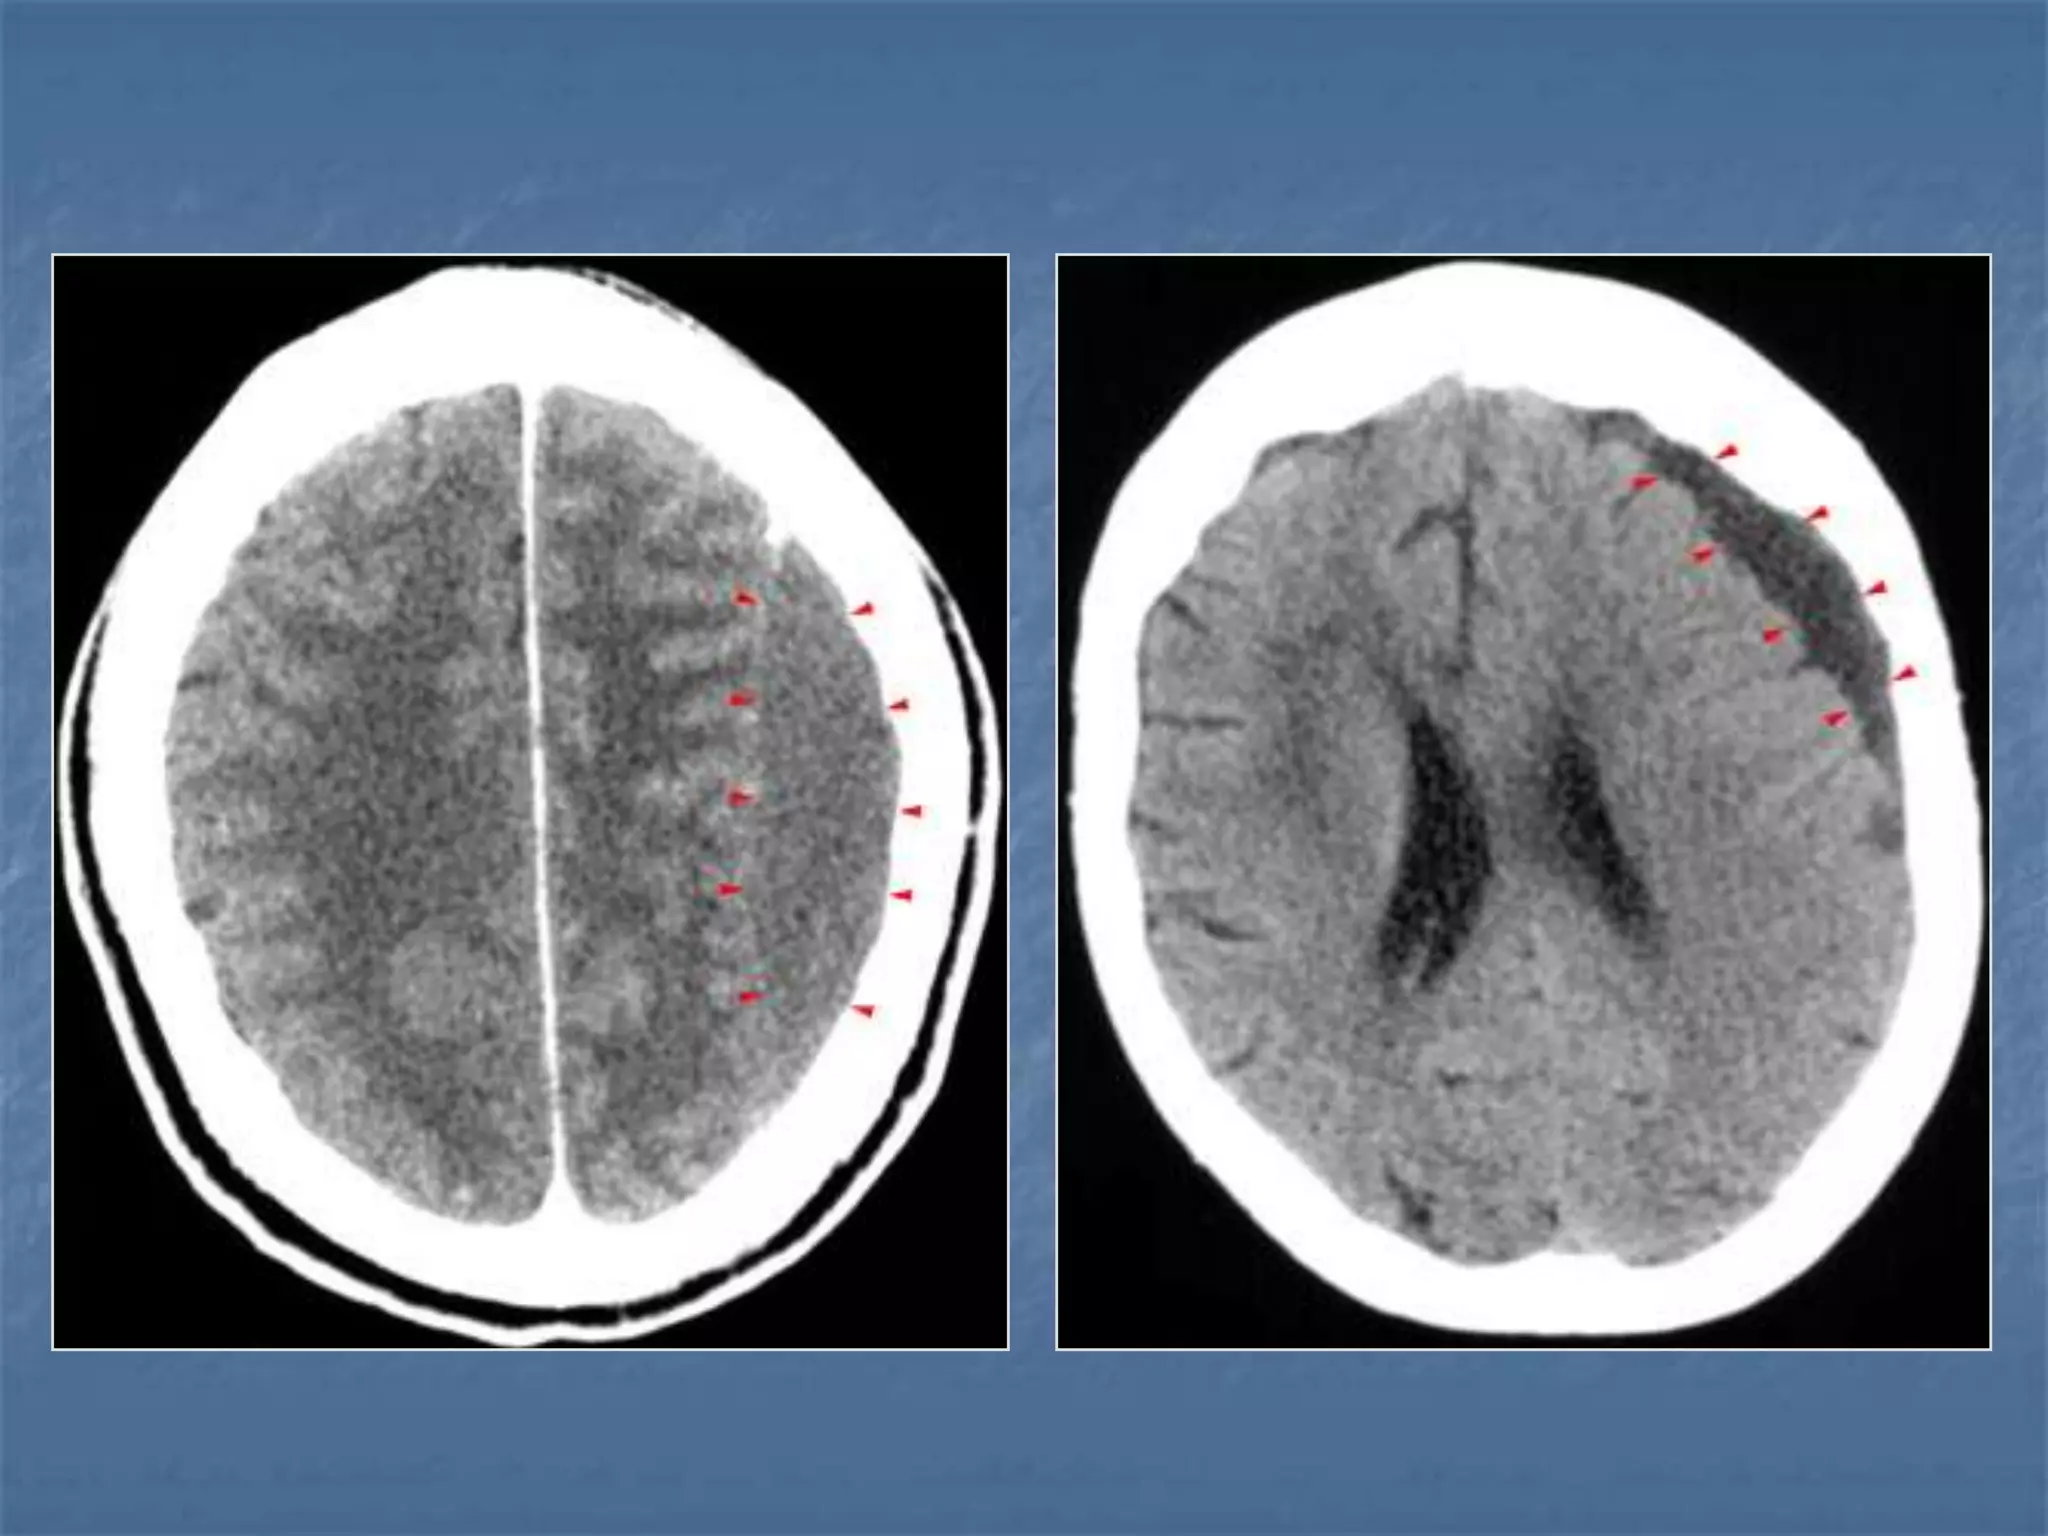

Venous Sinus Thrombosis with Venous

Infarct

 Clinical symptoms – head ache, seizures

 Pathology is due to decrease in perfusion pressure as

the venous pressures elevate due to occlusion.

 Predisposing conditions are dehydration, infection,

polycythemia, sickle cell disease, hypercoagulable

states, peripartum, OCP poisoning.

Imaging findings

 Unilateral / bilateral parenchymal hypodensities

 Not limited to an arterial territory

 May be associated with hemorrhage

 Signs: Delta sign, Enhancement of walls of sinus than

their contents.